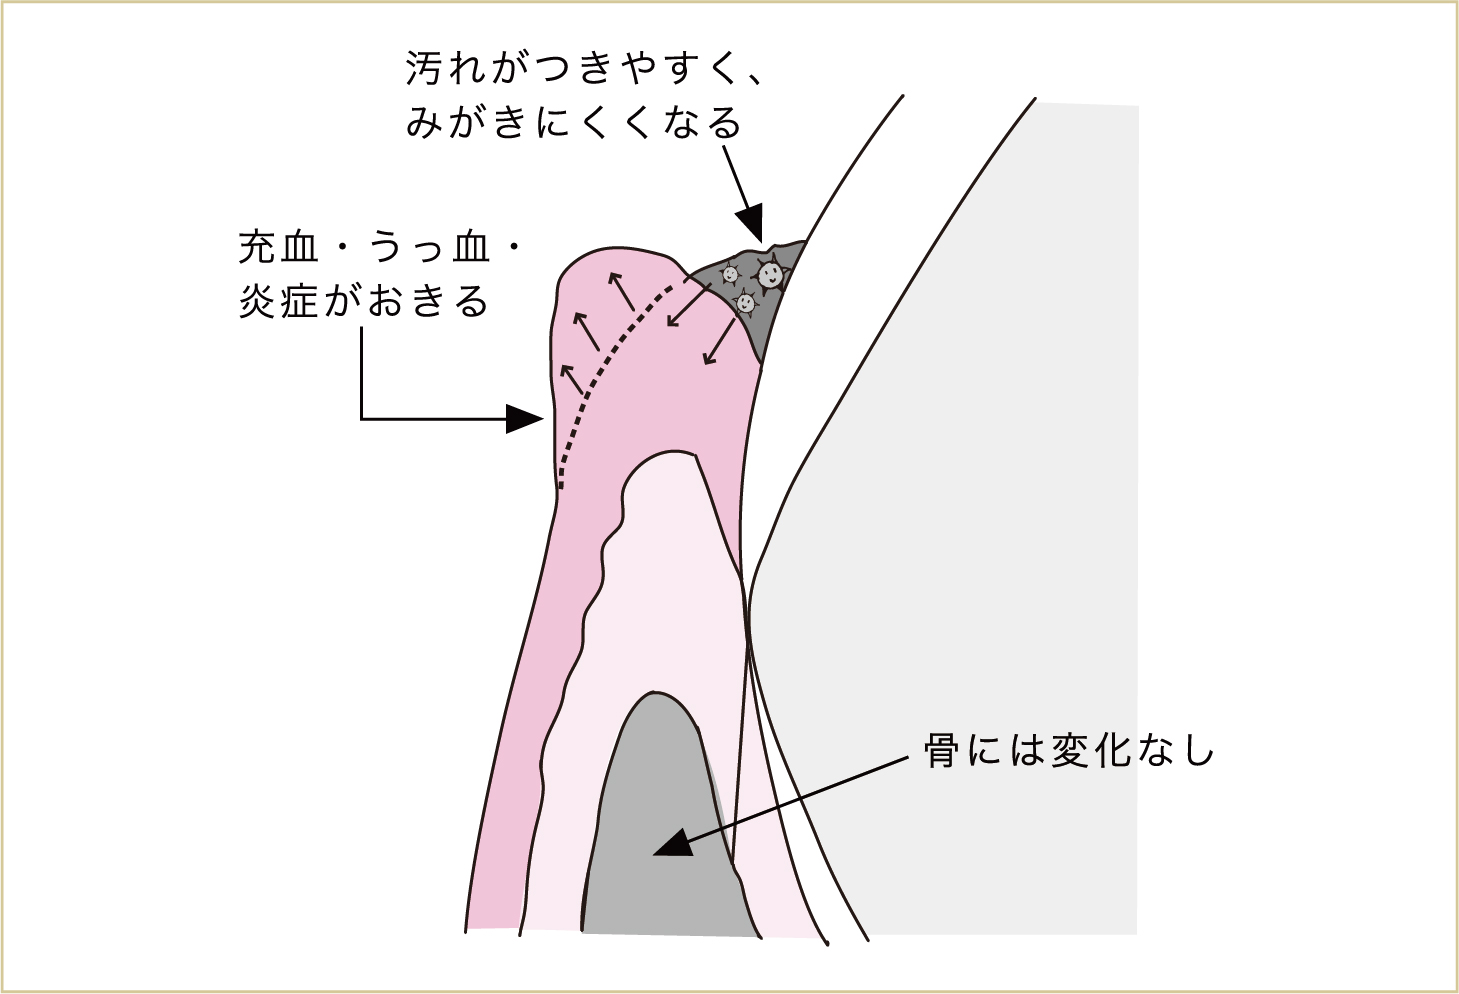

そうすると歯肉にはどんな変化が生じるのでしょう。そうです、歯肉が腫れて充血・うっ血してくるのです。歯肉は、この毒を洗い流すために、新しい血管をつくって新鮮な血液をたくさん流していきます。しかし大急ぎでつくられた血管は、壊れやすかったり血が出やすかったりするため、よけいにうっ血していきます。これが「歯肉炎」という状態です。

細菌の出す毒が歯肉に触れたり侵入したりすることで、歯肉が腫れてふくらみ、血が出やすくなって炎症が生じる。

歯肉が腫れることで、歯と歯肉の間の溝が深くなったりして、よりみがき残しができやすい状態になります。

そうして、ますます汚れが降り積もった結果、細菌たちが出す毒素の量も増加します。増加した毒素を洗い流すための血液も、さらにたくさん必要になってくるため、よりいっそう腫れてきます。

腫れた歯肉は、ますます汚れがつきやすく、みがき残しができやすい形になっていき、より多くの細菌による毒素が歯肉に影響を与えるようになる。